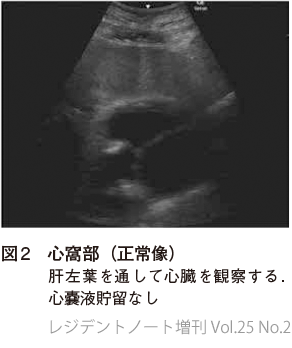

1. 心窩部像

EFASTではまず心窩部像で心嚢液貯留の有無を確認する.心嚢液貯留から心タンポナーデに至ると閉塞性ショックを呈するが,これは外傷において最も多い出血性ショックとは治療方針が大きく異なるため,その認知は重要である.なお,心嚢液貯留は心タンポナーデの必要条件であるが十分条件ではない.

心室壁よりも外側に液体貯留があるかどうか確認する(図2,3).